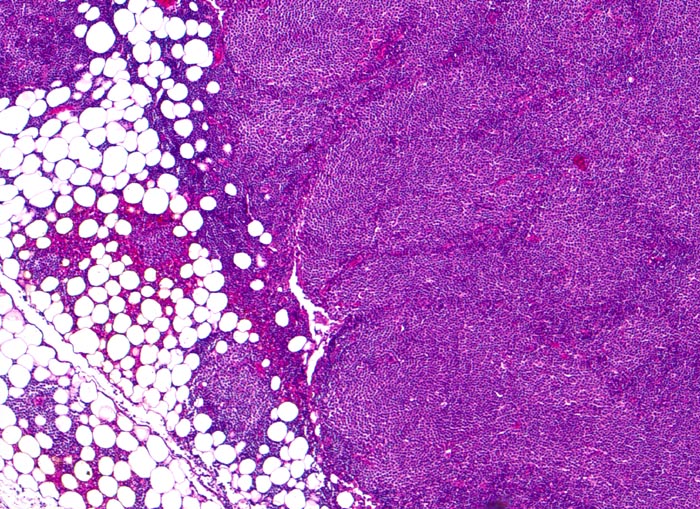

• Vergrösserter Lymphknoten mit zerstörter Lymphknotenarchitektur.

• Diffuse Infiltration des Lymphknotens durch monomorphe kleinlymphozytische Lymphomzellen.

• Übergreifen des neoplastischen Infiltrates auf das umgebende Fettgewebe.